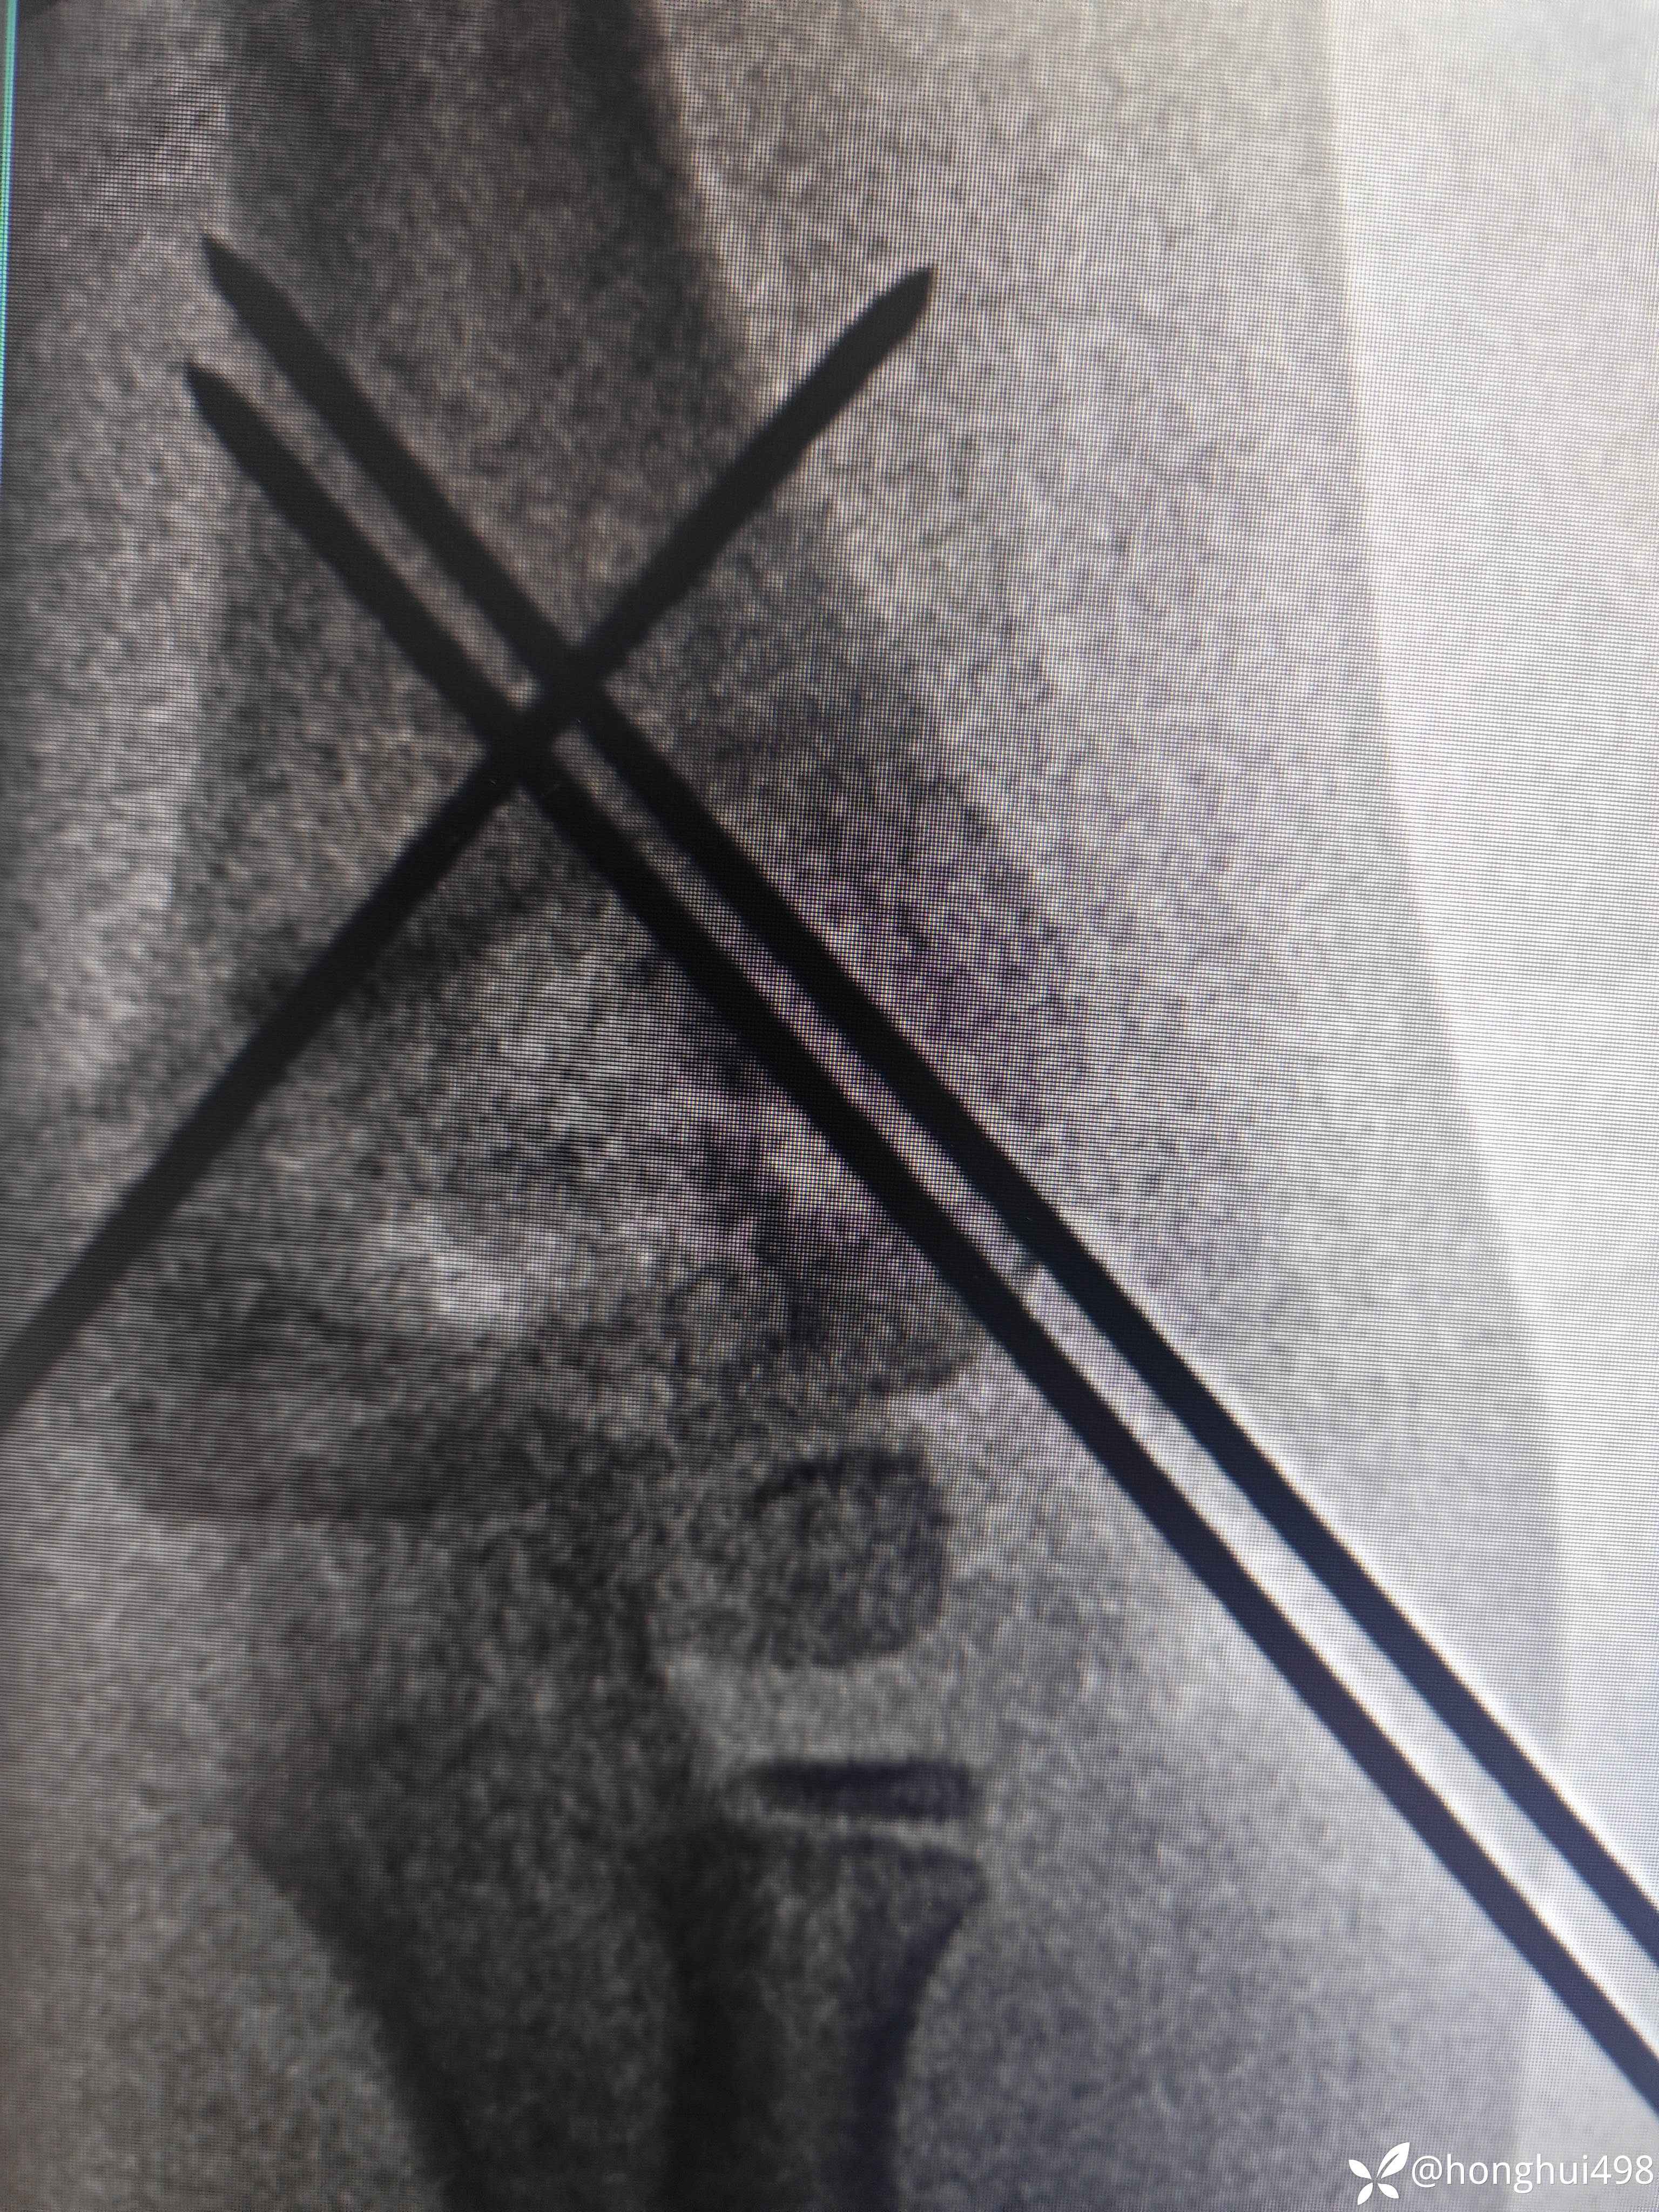

患儿女性,6岁,昨晚8点在家玩耍摔倒受伤,右肱骨髁上骨折。伤后在当地予手法复位草药外敷,伤后15小时来我院就诊,住院麻醉下闭合复位克氏针内固定。